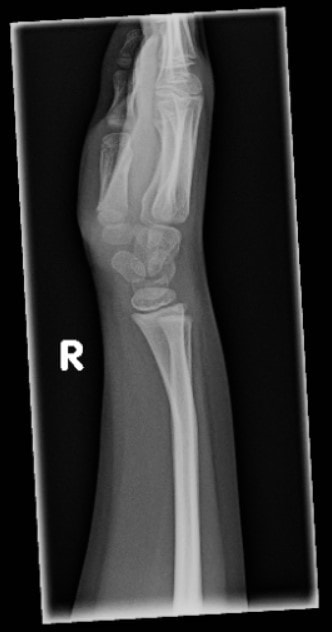

The patient is an 11-year-old boy who presents complaining of pain in his left and right forearm and wrist after falling from a height of approximately 5 feet. His parents report that he was attempting to hang upside down by his knees from a chin-up bar in his school’s gymnasium when he slipped.

View the images taken and consider what the diagnosis and next steps would be. Resolutions of the case is described on the next page.

An 11-Year-Old Boy with Forearm and Wrist Pain After a Fall